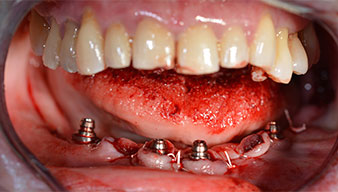

El siguiente ajuste programado es la propia inserción de los implantes. En nuestra clínica, solemos insertar los implantes con una fuerza de 32 Ncm de manera estándar (figs. 12 y 13).

El requisito imprescindible para el tratamiento inmediato es una alta estabilidad primaria. Para satisfacer dicho requisito, en este caso, se prescindió del corte de rosca. La unidad de accionamiento Implantmed de W&H empleada aquí, posee un modo propio para ello que también puede seleccionarse directamente y resulta imprescindible para muchas indicaciones. Los últimos giros para la inserción del implante superaron el valor de 32 Ncm, por lo que se realizaron manualmente. En tales casos, se recomienda utilizar la función autocortante de los implantes y girar el implante varias veces hacia delante y hacia atrás de forma que el implante se aproxime gradualmente hasta su posición definitiva sin ejercer una presión excesiva sobre el hueso (fig. 14).

Para compensar la divergencia de los implantes distales, se atornillaron pilares acodados (35 grados) de forma que los perfiles de emergencia de todos los implantes quedaran en la posición más vertical posible en relación con la mordida. Este paso es necesario para poder atornillar de forma oclusal el tratamiento provisional y, posteriormente, el definitivo (figs. 15 y 16).